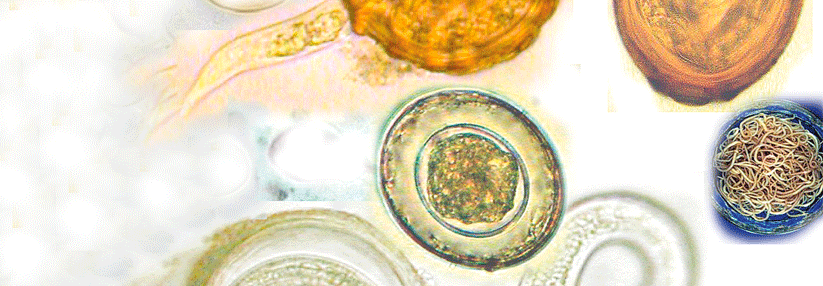

Die Larven der Dasselfliege leben obligat parasitisch. Je nach Art entwickeln sie sich in Nase, Rachen, Magen oder unter der Haut von Säugetieren. Die Larven der Dasselfliege leben obligat parasitisch. Je nach Art entwickeln sie sich in Nase, Rachen, Magen oder unter der Haut von Säugetieren. © wikimedia/Fritz Geller-Grimm; wikimedia/Petruss

Eine 13-jährige Schülerin ist vor 14 Tagen von ihrem Peru-Austausch zurückgekehrt. Schon seit Wochen plagt sie eine schmerzhafte Läsion an der Schulter mit einem wie ausgestanzt wirkenden, blutenden Loch in der Mitte und rätselhaftem Inhalt. Mithilfe einer Pinzette zieht Dr. Fölster-Holst in der Praxis eine Fliegenmade heraus. Das junge Mädchen hatte also Myiasis, ausgelöst durch die Dasselfliege (Dermatobia hominis). Das pelzig behaarte Insekt kommt in gro­ßen Teilen Süd­amerikas vor – auch in Peru.

Das Entfernen der Larve ist gleichzeitig kurativ, die Wunde heilt anschließend von selbst ab. Übertragen wird die „Fliegenmadenkrankheit“ durch den Stich einer „gewöhnlichen“ Mücke, an die eine adulte Dasselfliege zuvor ihre Eier geheftet hat.

Zerkarien sind die Larven von Saugwürmern, die nach ihren Haftorganen auf der Bauchseite benannt sind. Ist die Wassertemperatur hoch genug, werden sie von ihrem Zwischenwirt, verschiedenen Wasserschneckenarten, freigesetzt und können auch badende Menschen befallen, wenn sie sich in deren Haut bohren. Die Erkrankung wird auch Entenbilharziose genannt, da die Wasservögel der eigentliche Endwirt sind.